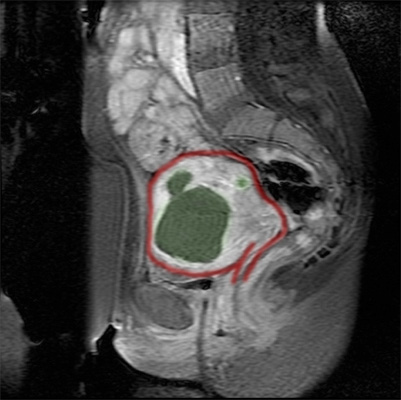

Studium przypadku 47-letniej pacjentki z kilkoma mięśniakami o średnicy do 5 cm.

Obrazy MRT bezpośrednio po dodaniu środka kontrastowego. Leczone mięśniaki nie są już ukrwione, w związku z czym nie przyjmują środka cieniującego i na obrazie mają kolor czarny.